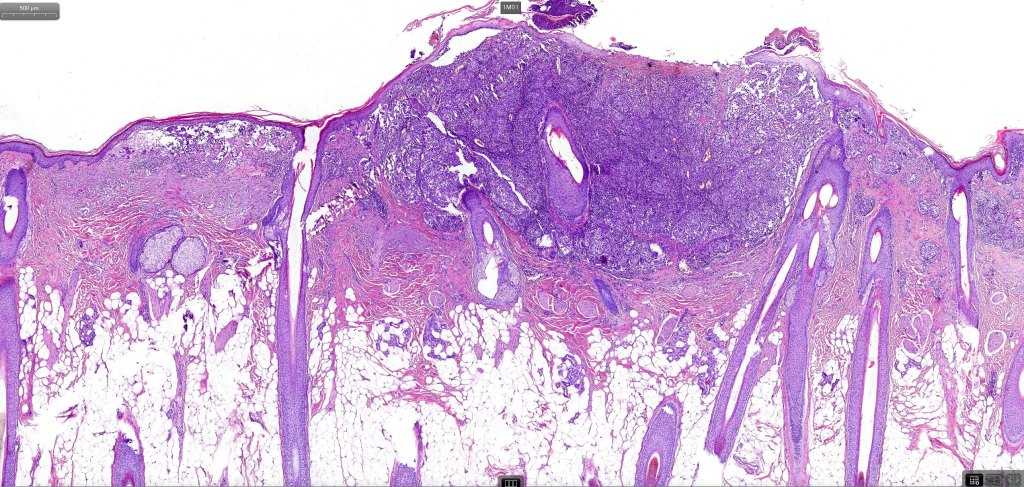

An exceedingly rare variant of melanoma. The term includes cases of melanoma that show features of an associated inherited bullous dermatosis such as epidermolysis bullosa or acquired immunobullous intraepidermal or sub epidermal bullous dermatosis such as pemphigus or bullous pemphigoid and cases where the blister develops directly overlying the melanoma in the absence of any underlying/associated blistering condition. It is generally recommended that measurement of the melanoma should be from taken below the blister/vesicle so as to avoid over-estimating tumor thickness.

Case courtesy of Dr. Antonina Kalmykova